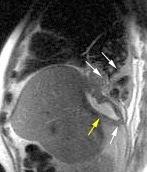

Marzo 2014: Perforación longitudinal distal secundaria a episodio de vómito (síndrome de Boerhaave). Derrame pleural izdo. que evoluciona a empiema.

Wang C-T et al. Tension hydropneumothorax in a Boerhaave syndrome patient: A case report . World J Emerg Med, 2021. Katabathina V et al. Nonvascular, nontraumatic mediastinal emergencies in adults:a comprehensive review of imaging findings. Radiographics. 2011.